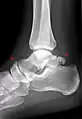

Os trigonum

The os trigonum or accessory talus represents a failure of fusion of the lateral tubercle of the posterior process of the talus bone. Is estimated to be present in 7–25% of adults.[17] It can be mistaken for an avulsion fracture of lateral tubercle of talus (Shepherd fracture) or a fracture of the Stieda process. In most cases, Os Trigonum will go unnoticed, but with some ankle injuries it can get trapped between the heel and ankle bones which irritates the surrounding structures, leading to Os Trigonum Syndrome.[21]